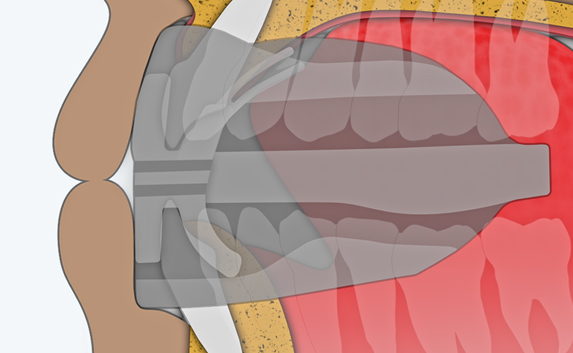

The Myosa®for TMJBDS®S1 is used in patients with a Breath Hold Time (BHT) of 20 seconds or more. It works by advancing the sleeper’s lower jaw and opening the bite, which has the effect of opening the airway. Additionally, the S1 has four breathing holes at the front to regulate breathing. For better retention during sleep, the patient can use the mouldable version of the S1 appliance (S1M). Progress to the S2 when the patient’s BHT reaches 35 seconds or more.